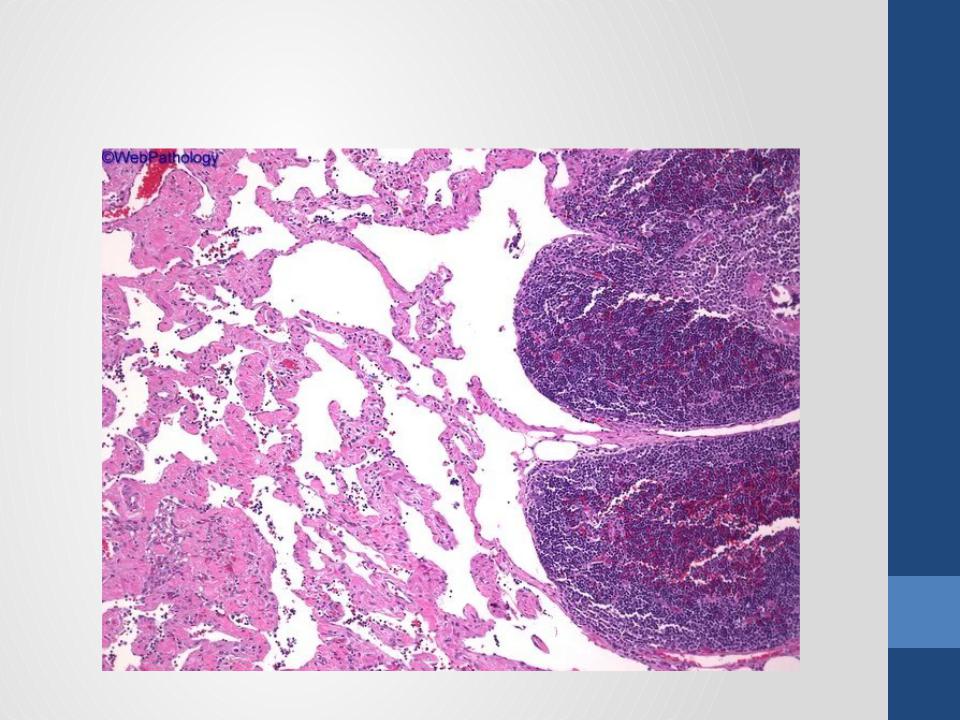

- •Гистологическая картина

- •Злокачественная аденолимфома с метастазом в лимфатический узел

- •Аденолимфомаслюнойжелезы (опухольОртина)

- •Аденолимфомаслюнойжелезы (опухольОртина)

- •Аденолимфомаслюнойжелезы (опухольОртина)